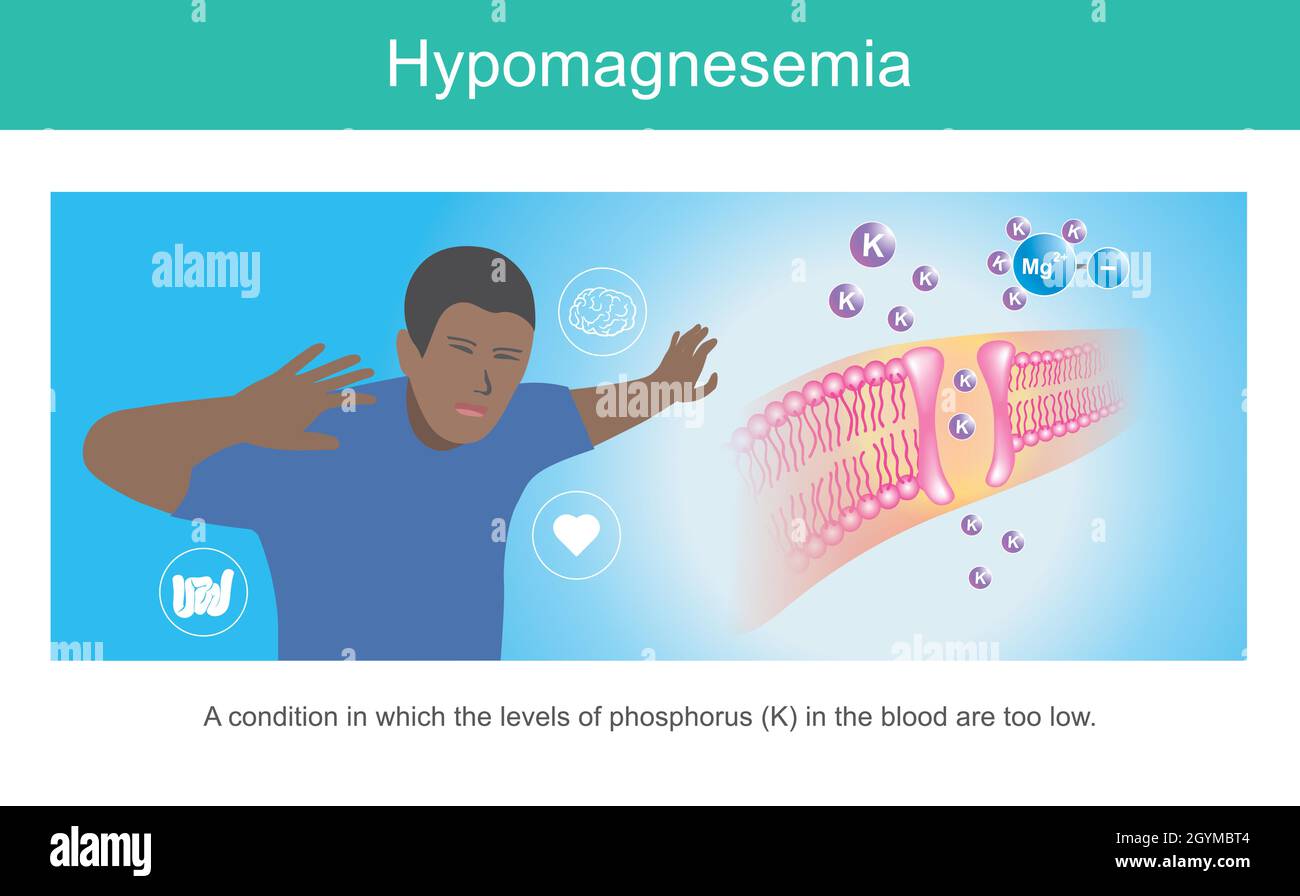

IPOMAGNESEMIA. Illustrazione per mostrare i sintomi una condizione dell'uomo in cui i livelli di fosforo nel sangue sono troppo bassi. Illustrazione Vettorialehttps://www.alamy.it/image-license-details/?v=1https://www.alamy.it/ipomagnesemia-illustrazione-per-mostrare-i-sintomi-una-condizione-dell-uomo-in-cui-i-livelli-di-fosforo-nel-sangue-sono-troppo-bassi-image447303252.html

IPOMAGNESEMIA. Illustrazione per mostrare i sintomi una condizione dell'uomo in cui i livelli di fosforo nel sangue sono troppo bassi. Illustrazione Vettorialehttps://www.alamy.it/image-license-details/?v=1https://www.alamy.it/ipomagnesemia-illustrazione-per-mostrare-i-sintomi-una-condizione-dell-uomo-in-cui-i-livelli-di-fosforo-nel-sangue-sono-troppo-bassi-image447303252.htmlRF2GYMBT4–IPOMAGNESEMIA. Illustrazione per mostrare i sintomi una condizione dell'uomo in cui i livelli di fosforo nel sangue sono troppo bassi.